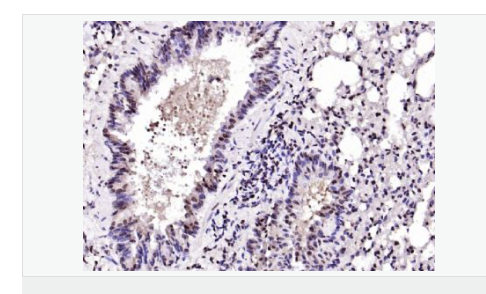

| 產(chǎn)品應(yīng)用 | ELISA=1:5000-10000 IHC-P=1:100-500 IHC-F=1:100-500 IF=1:100-500 (石蠟切片需做抗原修復(fù)) not yet tested in other applications. optimal dilutions/concentrations should be determined by the end user. |